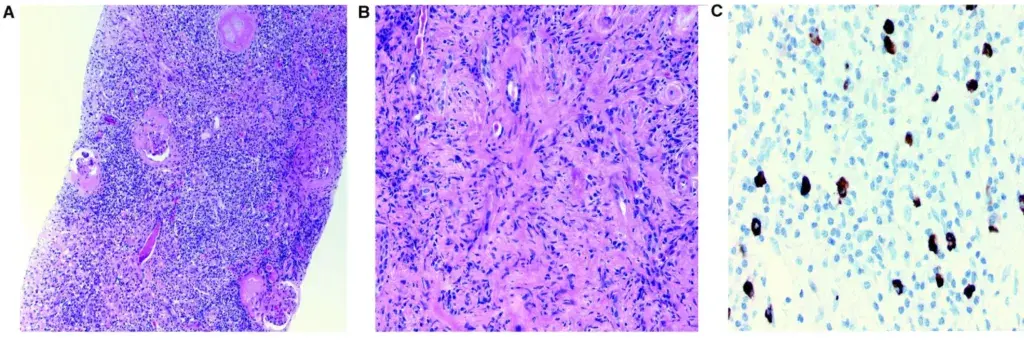

**Realizado biópsia renal** que evidenciou infiltrado intersticial intenso e difuso composto por linfócitos e plasmócitos envolvendo >70% do interstício (Figura). Identificado também fibrose estoriforme no interstício

Diante dos achados foi realizado a imunohistoquímica para IgG e IgG4 sendo evidenciado áreas focais com >10 células plasmáticas IgG4+/campo. Essa combinação de achados foi considerada consistente com o diagnóstico de **nefrite tubulointersticial relacionada a IgG4**.

Figura: Principais achados da biópsia renal para nefrite tubulointersticial relacionada a IgG-4. (A) Infiltrado denso de plasmócitos e linfócitos à microscopia de luz (coloração HE). (B) Fibrose estoriforme com aspecto de “cartwheel” é observada na microscopia de luz (coloração HE). (C) Células positivas para IgG4 são observadas em mais de 10 células por campo (imunohistoquímica para IgG4).

Os achados patológicos incluem um **infiltrado linfoplasmocitário**, **fibrose estoriforme**, **flebite obliterante** e **infiltrados de plasmócitos IgG4+**.

- A histologia revela um infiltrado intersticial linfoplasmocítico dominante com marcação para IgG4. Fibrose estoriforme e flebite obliterativa podem ser observadas.